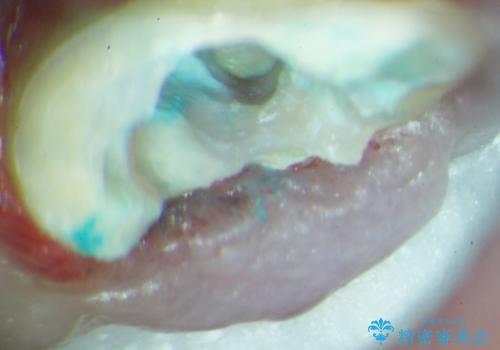

歯を牽引し健全歯質を歯肉縁上まで引き上げ、歯の保存を試みることにしました。

歯の牽引後、ブリッジの仮歯で保定しながら歯肉・骨の治癒を待ったのち、ブリッジによる補綴を行いました。

健全歯質を歯肉縁上に出すためにしっかり挺出させたことで歯根長が短くなりましたが、仮歯で十分に保定した結果動揺度Ⅰ程度となり、ブリッジの支台歯にすることが可能と判断しました。